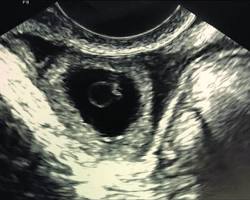

5-week pregnancy ultrasound showing the dark gestational sac and the white ring of the yolk sac

The Early Window: Seeing the yolk sac is the first confirmation that the pregnancy is developing inside the uterus.

The Yolk Sac is the first structure to appear inside the dark gestational sac. It provides all the nutrients the embryo needs until the placenta is fully functional in the second trimester. Seeing the yolk sac this week is a huge milestone, as it confirms the pregnancy is in the correct location.